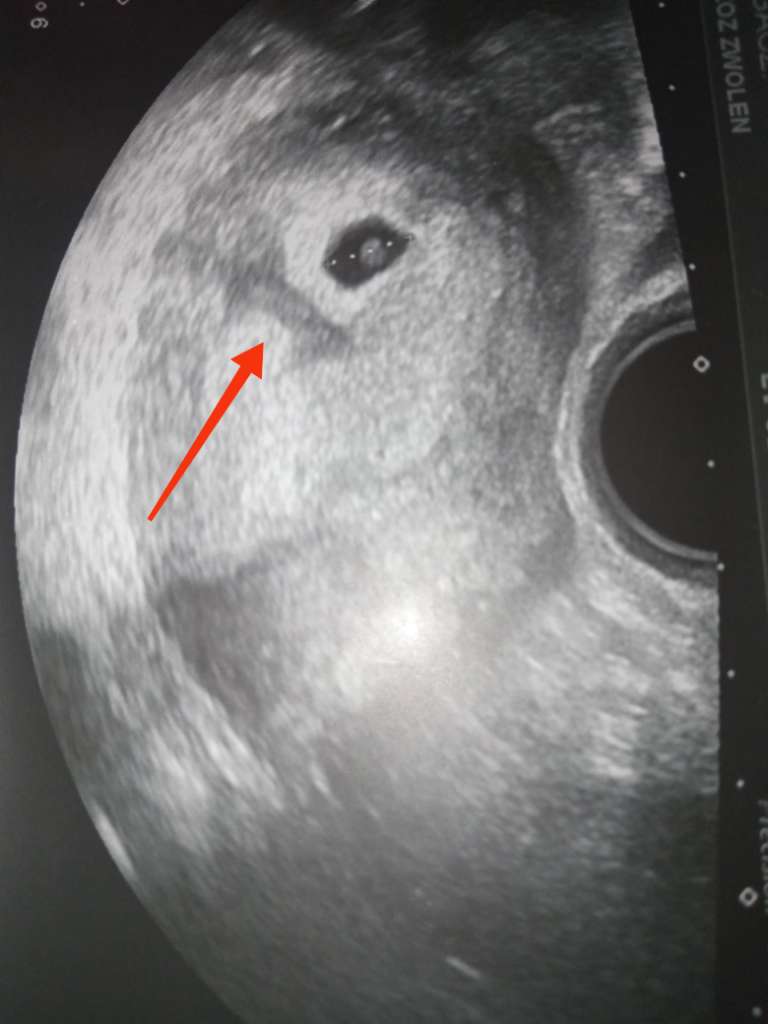

Cześć byłam dziś na wizycie u ginekologa wyszło że jestem jakoś w 5 tyg i 3 dni, lekarz zobaczył na USG taką jakby zatoczkę jest ona na pierwszym zdjęciu i przepisał mi duphaston bo uważa że to łożysko się zaczyna odklejać... Kazał się oszczędzać, będzie ciężko patrząc na to że mam dwuletnie dziecko w domu. Powiedziałam mu też że mam bóle podbrzusza. Wiem że nie jesteście lekarzami, ale na tym USG serio to tak wygląda ? Chodzi o tą jakby plamkę co jest pod tym całym łożyskiem, boje się że coś się stanie.

znaczy po prostu nie będę go brała na ręce, tak to nie jest mały aż taki zły haha dokucza trochę. Właśnie myślę czy mi dał to przez tą plamę czy przez to że mu powiedziałam że mnie boli podbrzusze trochę, ale on spojrzał na USG i powiedział że to wygląda tak jakby groziło poronienie właśnie przez tą plamkę...

szczerze mówiąc to już sama nie rozumiem... Mówił po prostu że ciąża moze się nie utrzymać bo to wygląda jakby się odklejało...